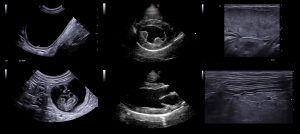

- Uovertruffen bildekvalitet på mikrokonveks og hjerteprober

Nye prober fra Esaote med patentert design. De er produsert i composite materiale med ny multi-layer teknologi. De gir fantastisk høyoppløselige bilder og økt doppler sensitivitet for hjerteundersøkelser, MSK og generell abdomen. Probene leveres med ny doppler teknologi: MicroV, som gir en enestående følsomhet selv i små kar og ved deteksjon av lavere hastigheter. MicroV har en algoritme som helt overlegent separerer bevegelse av væske fra andre bevegelser som skaper forstyrrelser. Med MicroV er det mulig å endre visualiserings algoritme for å forsterke ytterligere det du ønsker å se.

Garanterer et veldig høyt nivå på bildekvalitet i alle veterinære applikasjoner. Dedikert vet. programvare og nye prober gir deg mulighet for nøyaktig diagnose raskere enn før.

Ny doppler teknologi: MicroV.

MicroV, den nyeste dopplerteknologien fra Esaote med en enestående følsomhet selv i små kar og deteksjon av lave hastigheter. MicroV er en algoritme som helt overlegent separerer bevegelse av væske fra andre bevegelser som skaper forstyrrelser. Dette gir en helt unik dopplerfølsomhet ikke sett tidligere. Med MicroV er det mulig å endre visualiserings algoritme for å forsterke ytterligere det du ønsker å se.